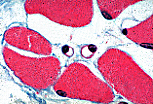

• Observation de capillaires continus

Observation en M.O.

Coupes transversales

En C.T., le diamètre des capillaires sanguins continus est comparable à celui d'un noyau d'une cellule musculaire striée squelettique (5 à 9 µm). Leur paroi est constituée d'une ou deux cellules endothéliales enroulées sur elles-mêmes.

Lorsque le plan de section passe en dehors du noyau de la cellule endothéliale, seul un anneau cytoplasmique éosinophile s'observe.

Si le noyau est dans le plan de la coupe, il apparaît incurvé selon la courbure du capillaire.

Le noyau de la cellule endothéliale peut parfois faire hernie dans la lumière du capillaire.

On devine la présence d'une lame basale autour de l'endothélium. Mais cette coloration trichromique et ce grossissement ne permettent pas de la distinguer nettement.

Les plus gros capillaires sanguins peuvent montrer en C.T. deux noyaux de cellules endothéliales. Au delà de ce nombre, on considère arbitrairement que le vaisseau est une veinule.

Des cellules périvasculaires, appelées péricytes, s'observent parfois enclavées dans la lame basale péri-endothéliale.

Leur noyau triangulaire fait saillie sur le versant exoluminal et semble coiffer  le capillaire.